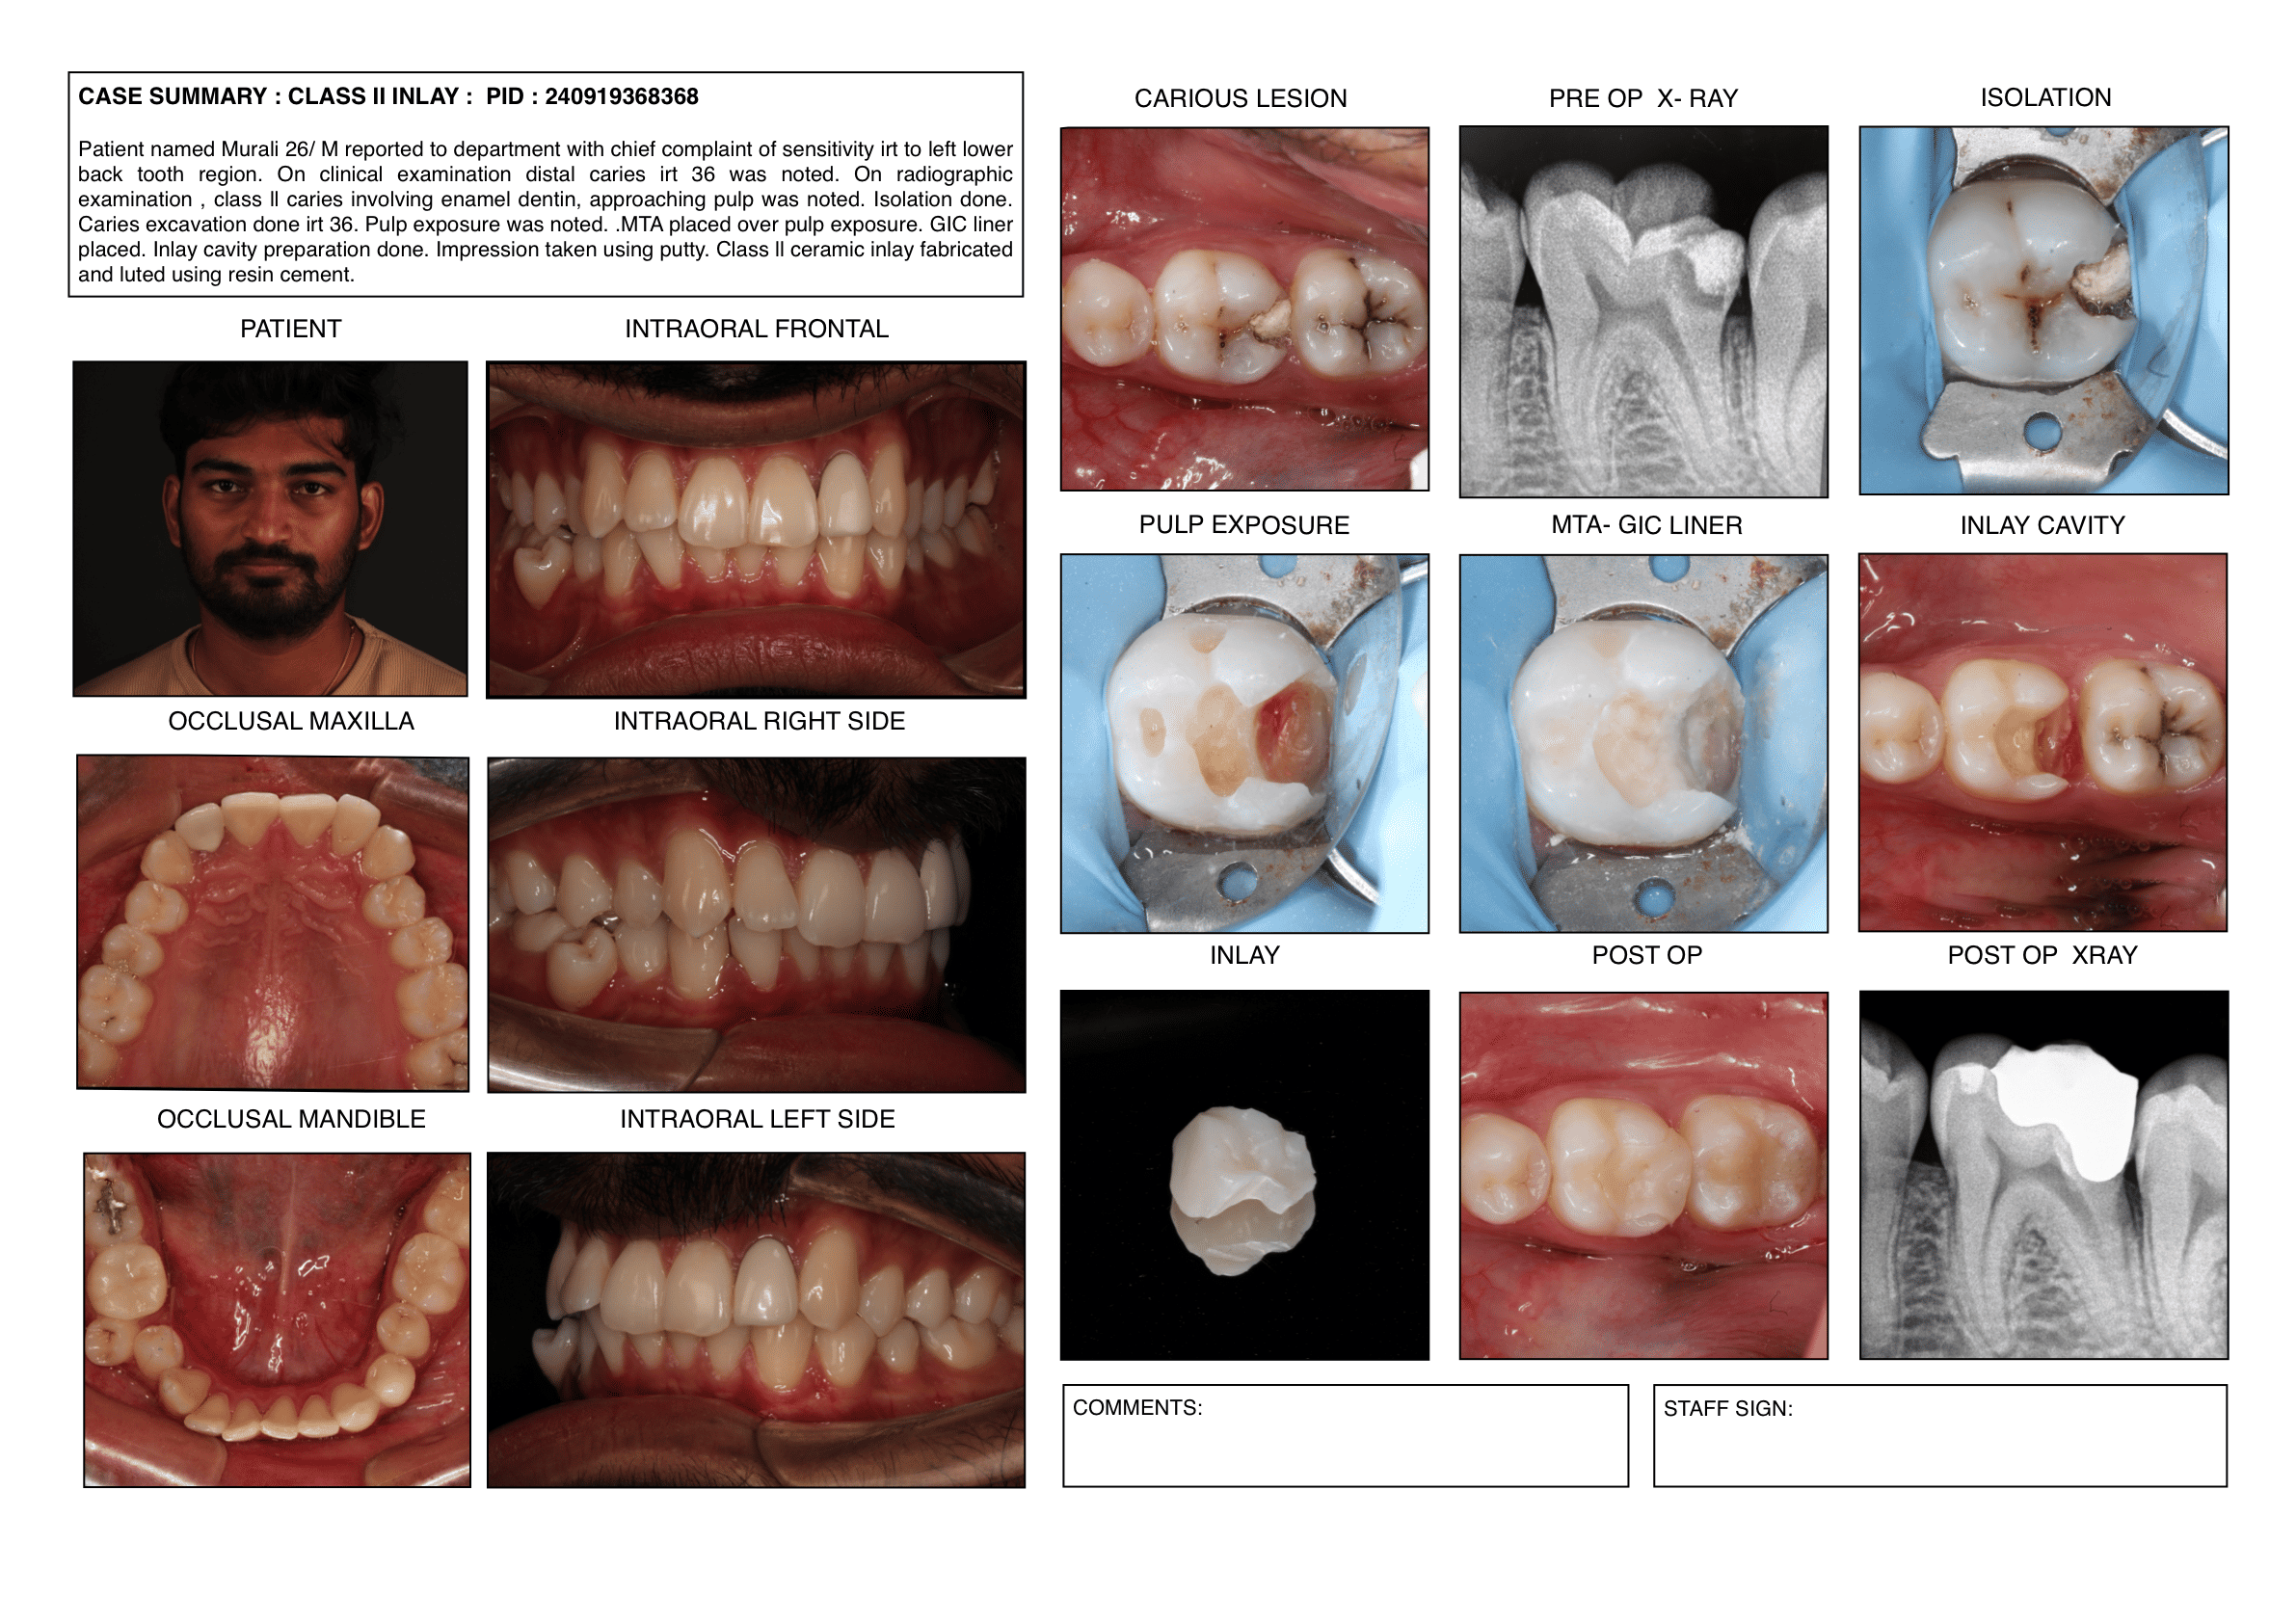

Endodontic cases